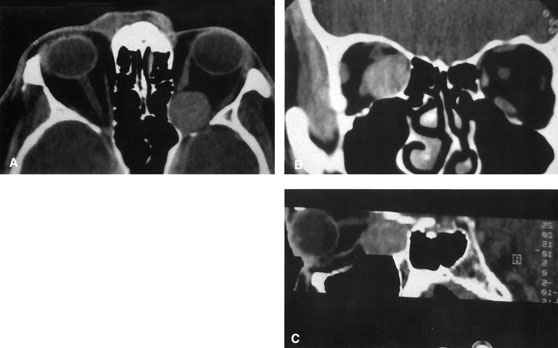

Fig. 25. A,B. Coronal (A) and axial (B) CT scans demonstrating well-encapsulated mass posteriorly in the superonasal orbit. An excellent alternative to transcranial orbitotomy for this lesion is an anterior approach via a vertical-lid splitting incision.

COMBINED APPROACHES